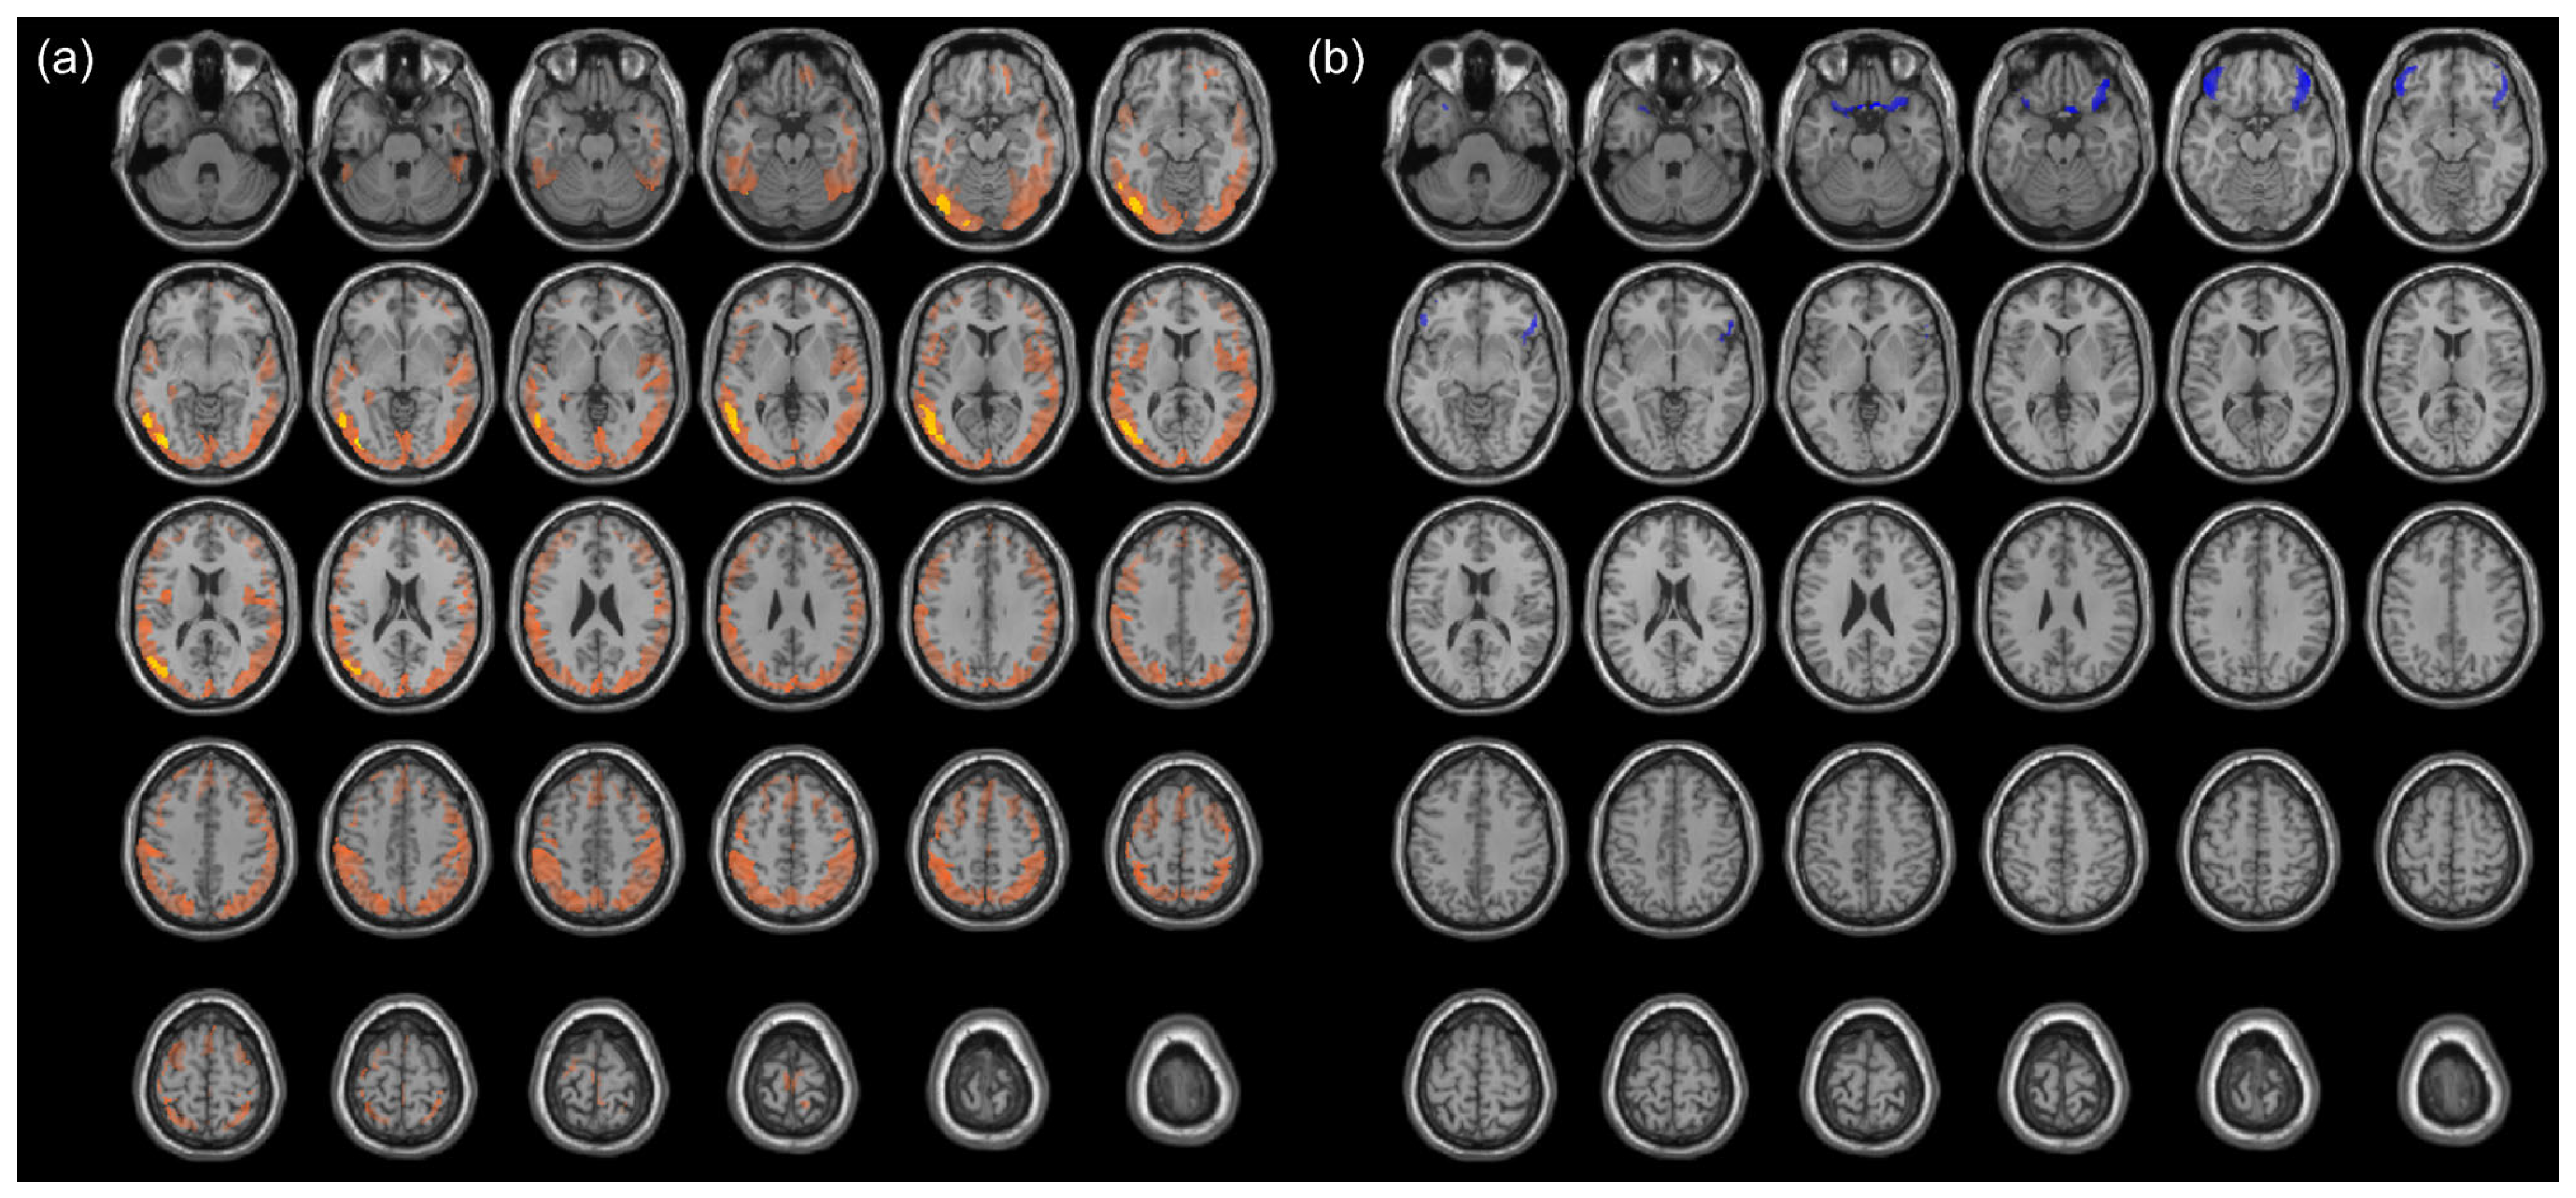

3.2. Cancer-Induced Changes in Cerebral Metabolism

3.3. Chemotherapy-Induced Change in Cerebral Metabolism